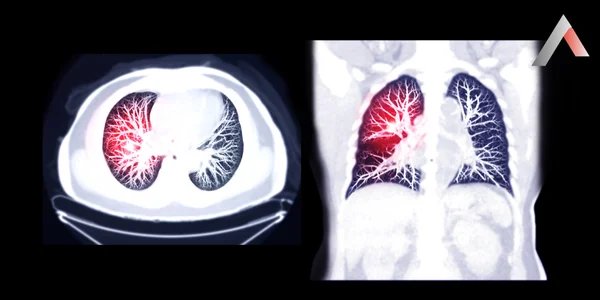

Akciğer embolisi, akciğerlerdeki bir veya daha fazla damarın kan pıhtısı tarafından tıkanması sonucu oluşan ciddi ve potansiyel olarak hayati tehlike yaratan bir durumdur. Bu pıhtı genellikle bacaklardaki veya pelvisteki derin venlerde oluşur ve kan dolaşımı ile akciğerlere taşınır. Akciğer damarlarının tıkanması, kalbin vücuda oksijen pompalama yeteneğini azaltır ve akciğer dokusunda hasara yol açabilir.

Akciğer embolisi, akciğerlerdeki bir veya daha fazla damarın kan pıhtısı tarafından tıkanması sonucu oluşan ciddi bir durumdur. Bu pıhtı genellikle bacaklardaki veya pelvisteki derin venlerde oluşur ve derin ven trombozu (DVT) olarak adlandırılır. DVT'den kopan pıhtı, kan dolaşımı ile akciğerlere taşınır ve akciğer damarlarını tıkar.

Akciğer damarlarının tıkanması, kalbin vücuda oksijen pompalama yeteneğini azaltır ve akciğer dokusunda hasara yol açabilir. Bu durum, nefes darlığı, göğüs ağrısı ve diğer ciddi belirtilere neden olabilir. Tedavi edilmezse, akciğer embolisi hayati tehlike yaratabilir.

• Bilgisayarlı tomografi (BT) pulmoner anjiografi: Akciğer damarlarını görüntülemek ve pıhtıları tespit etmek için en sık kullanılan testtir.

• Ventilasyon/perfüzyon (V/Q) taraması: Akciğerlerdeki hava akışı ve kan akışını değerlendirir. BT anjiografisi yapılamayan hastalarda tercih edilebilir.

• Akciğer anjiografisi: Akciğer damarlarını görüntülemek için en kesin yöntemdir, ancak invaziv bir işlem olduğu için nadiren uygulanır.